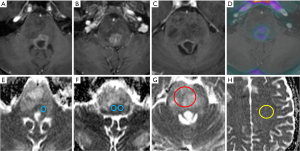

The median interval between the imaging and tissue diagnosis was 9 days (range, 0–74 days). Table 1 shows the ADC values obtained in 15 gliomas. The solid tumour ROI ADCmin results measured a mean of 0.84 (±0.15 standard deviation, SD) ×10-3 mm2/s. The solid tumour ROI ADCmean values within the largest cross-section had a mean of 1.12 (±0.25)×10-3 mm2/s. A mean of 0.76 (±0.06)×10-3 mm2/s was observed for the ADCNAWM values. The ROI ADCmin/NAWM ratio values measured a mean of 1.097 (±0.149), and for the ROI ADCmean/NAWM ratio the mean was 1.466 (±0.299). Table 2 shows the results of the volumetric ADC histogram measurements. Figure 2 shows an example of different ADC histogram curves observed in the H3 K27M mutant glioma cohort. A biphasic ADC distribution was evident in 2 histograms, with one glioma (case 2) showing a high volumetric ADCmean (3.54 mm2/s), likely due to inadvertent inclusion of necrotic tissue. In one glioma (case 8), no histogram could be produced due to missing data. A significant difference (P=0.01) was only observed between the 2nd centile of the volumetric ADC histogram and the ROI ADCmin values. The comparisons between ROI ADCmin and the 5th and 10th histogram percentiles showed no statistical difference (P=0.379 and P=0.177, respectively). No difference was observed between ROI ADCmin/NAWM ratio and the ADC5th percentile/NAWM ratio measurements (P=0.421). The comparisons between ROI ADCmean and the histogram ADCmedian and ADCmean were non-significant (P=0.576 and P=0.208). And no statistical difference was apparent between ROI ADCmean/NAWM ratio and the histogram ADCmean/NAWM ratio (P=0.60).

An overview of conventional imaging features is shown in Table 3. All H3 K27M-mutant gliomas were in contact with the brain midline (Figure 3). The lesion volumes ranged from 9.2 to 103.1 cm3. The definition of the non-contrast enhancing tumour margin appeared variable, whereby most lesions demonstrated heterogeneous T2/FLAIR signal. The observed T2/FLAIR heterogeneity corresponded to visible differences in ADC signal, with facilitated diffusion shown in necrotic glioma components. None of the H3 K27M histone-mutant gliomas exhibited a T2-FLAIR mismatch sign. Several tumours contained haemorrhagic components (Figure 4), whereas calcification was not identified, and only two tumours contained cysts. Rim-enhancement surrounding necrosis was present in 10/15 (67%) gliomas; 6/15 (40%) patients required shunting for hydrocephalus. Two gliomas were imaged with dynamic susceptibility contrast enhanced (DSC) perfusion MRI (Figure 5), which revealed elevated relative cerebral blood volume (rCBV) indicative of neovascularity. In one case, 18F-choline PET imaging was performed, showing radioactive tracer accumulation within enhancing tumour components (Figure 6).